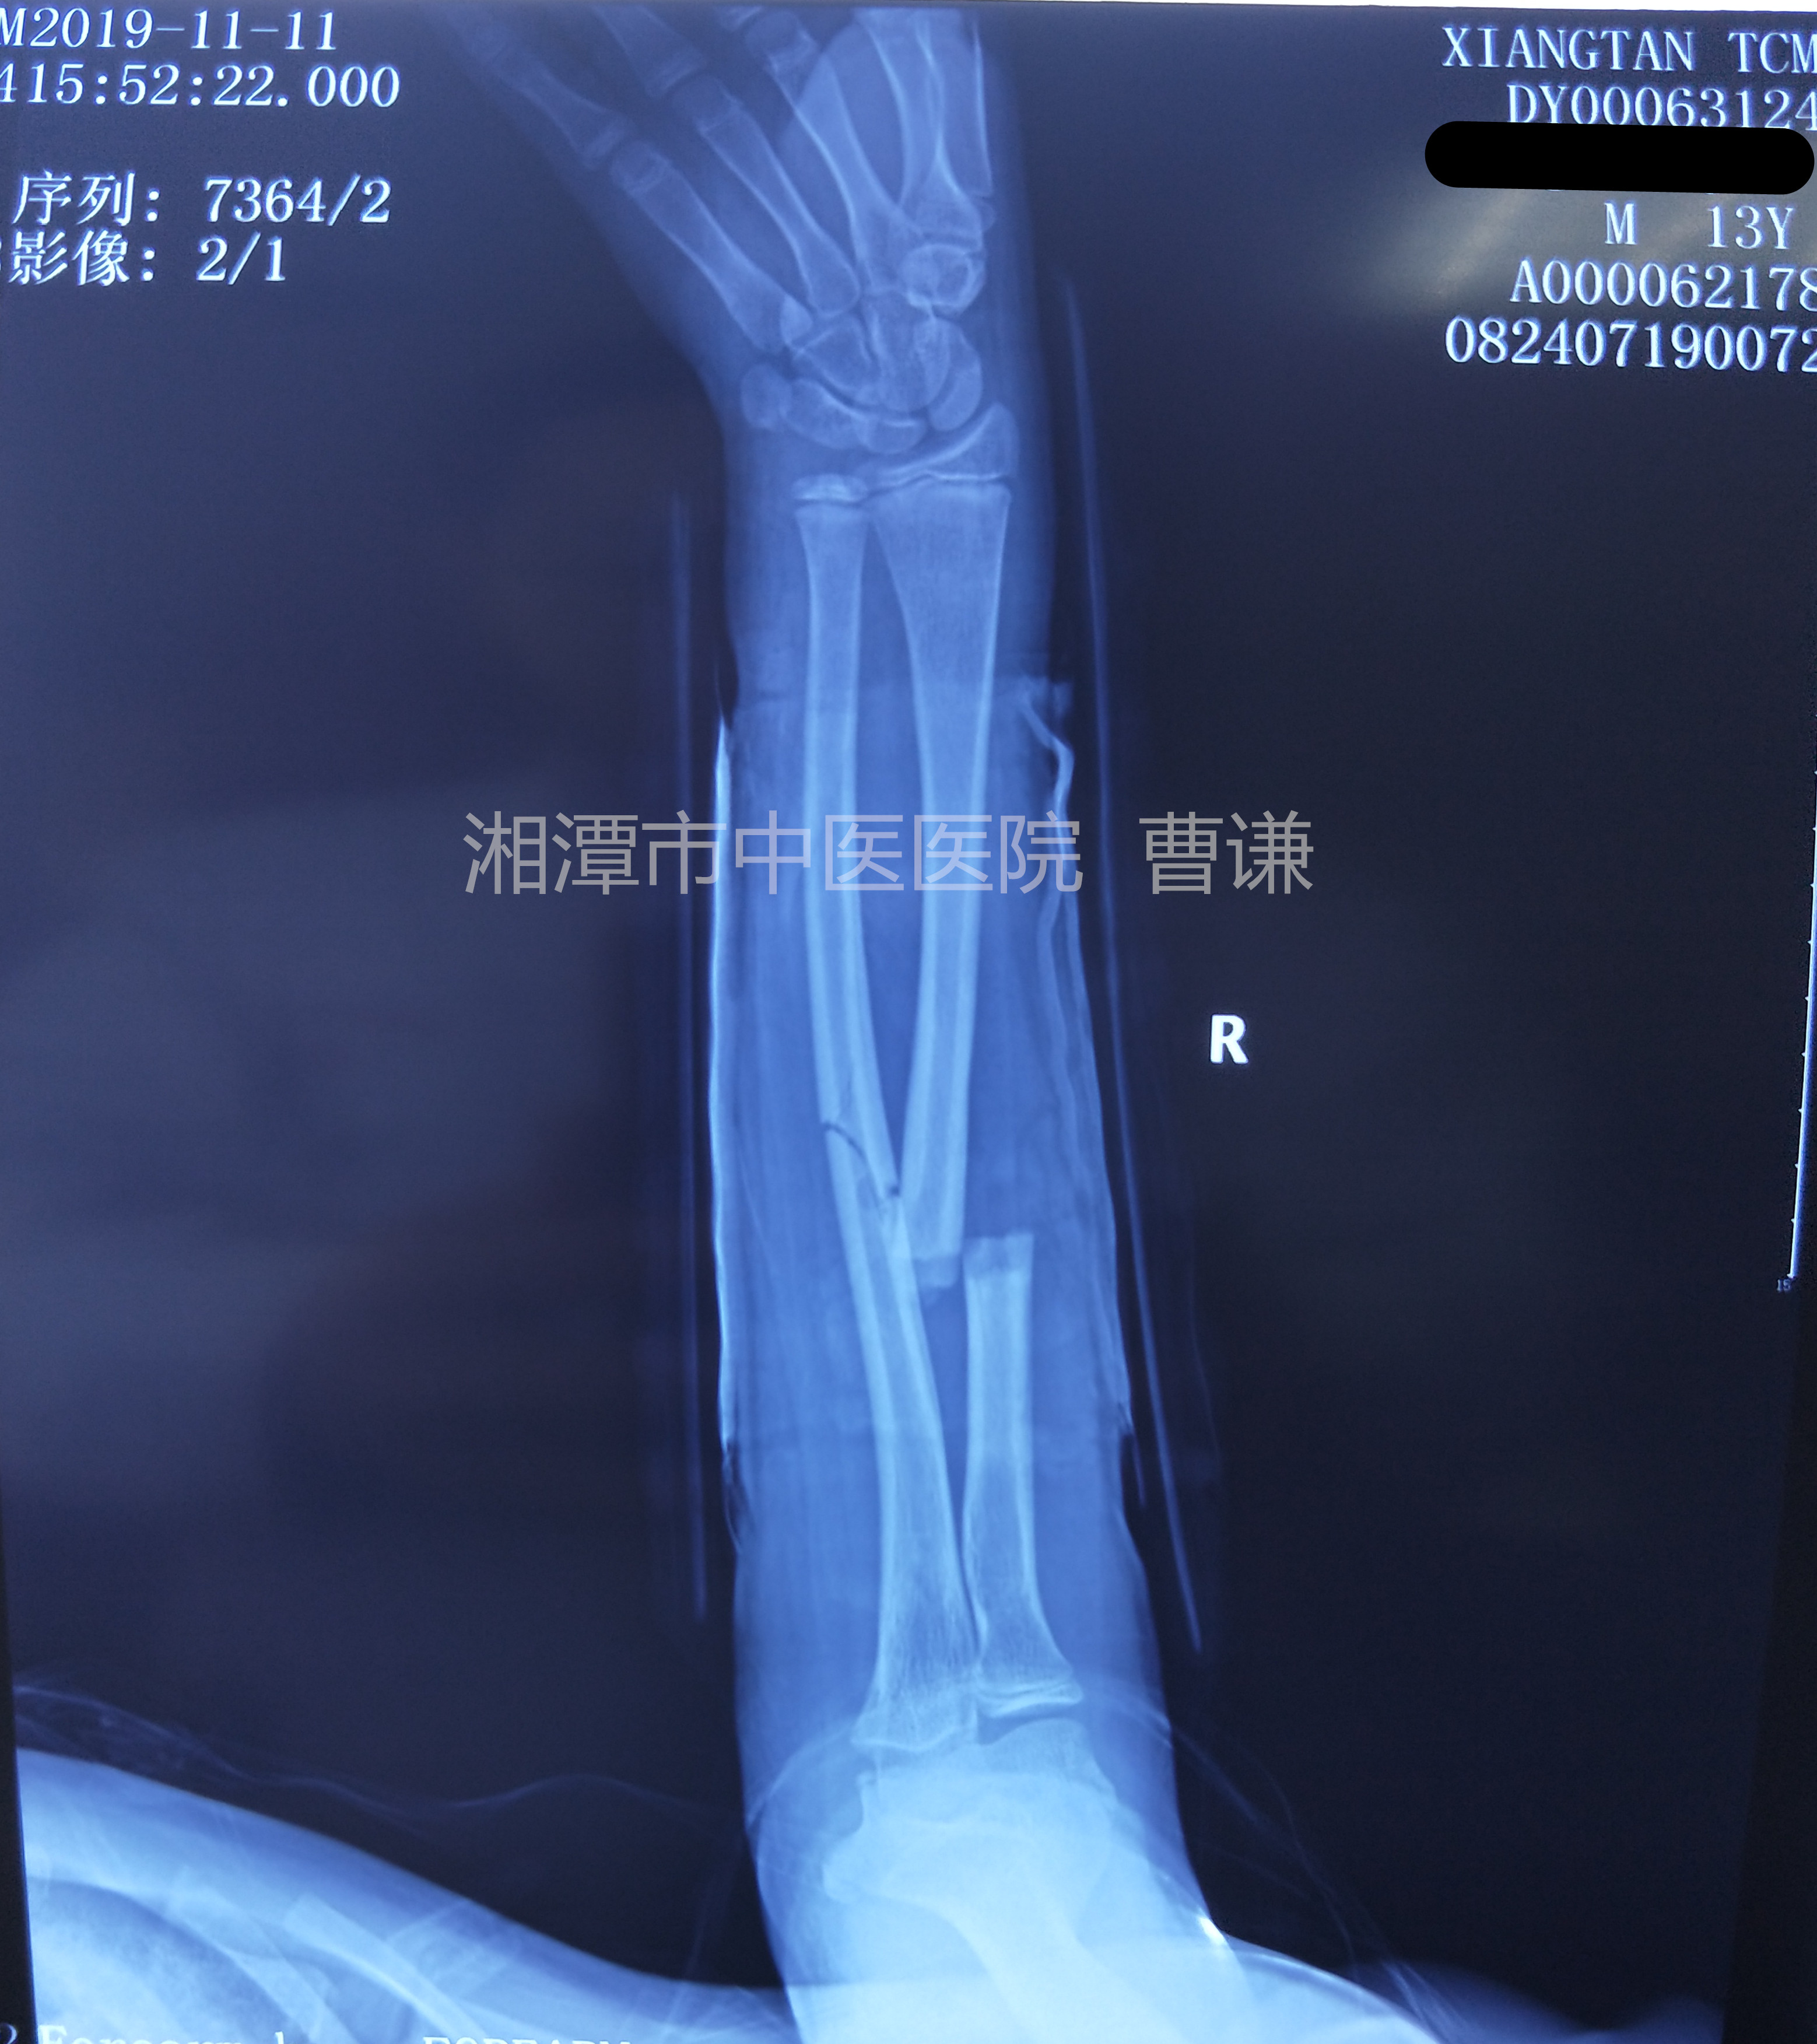

固定后拍片复查,是不是觉得比之前的片子对位对线情况更差了?有问题吗?没有问题,可以继续保守治疗!